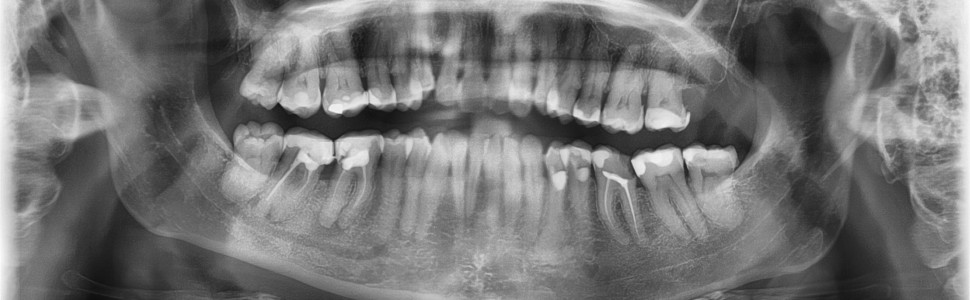

Sukces leczenia endodontycznego zębów zależy przede wszystkim od chemo-mechanicznego opracowania kanałów i szczelnego wypełnienia ich światła na pełnej długości. Zdarza się, że lekarz nie jest w stanie dotrzeć narzędziem do okolicy otworu wierzchołkowego. Celem pracy jest zaprezentowanie przypadków klinicznych, w których nie uzyskano pełnej długości roboczej kanałów za pomocą narzędzi, a mimo to kanały korzeniowe zostały wypełnione do części wierzchołkowej dzięki zastosowaniu techniki ciśnieniowej.

The success of endodontic treatment of teeth depends primarily on the chemo-mechanical preparation of the canals and tight fi lling of their lumen along their full length. It happens that the doctor is not able to reach the root tip mechanically. The aim of the study is to present clinical cases in which the full working length of the canals was not obtained with the use of tools, and yet the root canals were fi lled to the apical part thanks to the pressure technique.